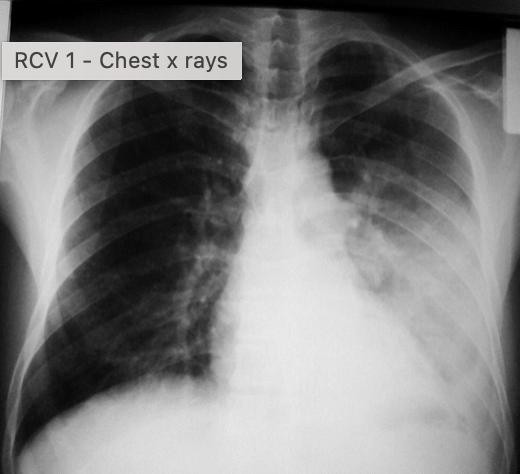

what is an effusion?

an accumulation of fluid in an anatomic space

Q

-check the lung fields - compare left to right lung

-are the volumes of the lungs equal?

-are there any differences overall?